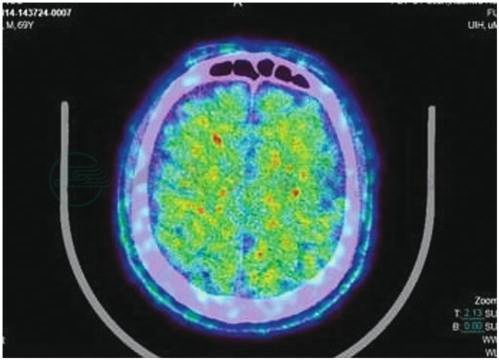

CT检查见脑萎缩、脑室扩大;头颅MRI检查显示的双侧颞叶、海马萎缩(图3)。SPECT灌注成像和氟脱氧葡萄糖PET成像可见顶叶、颞叶和额叶,尤其是双侧颞叶的海马区血流和代谢降低。使用各种配体的PET成像技术(如PIB-PET、AV45-PET)可见脑内的Aβ沉积(图4)。

图4 18F-AV45 PET显示脑内Aβ沉积